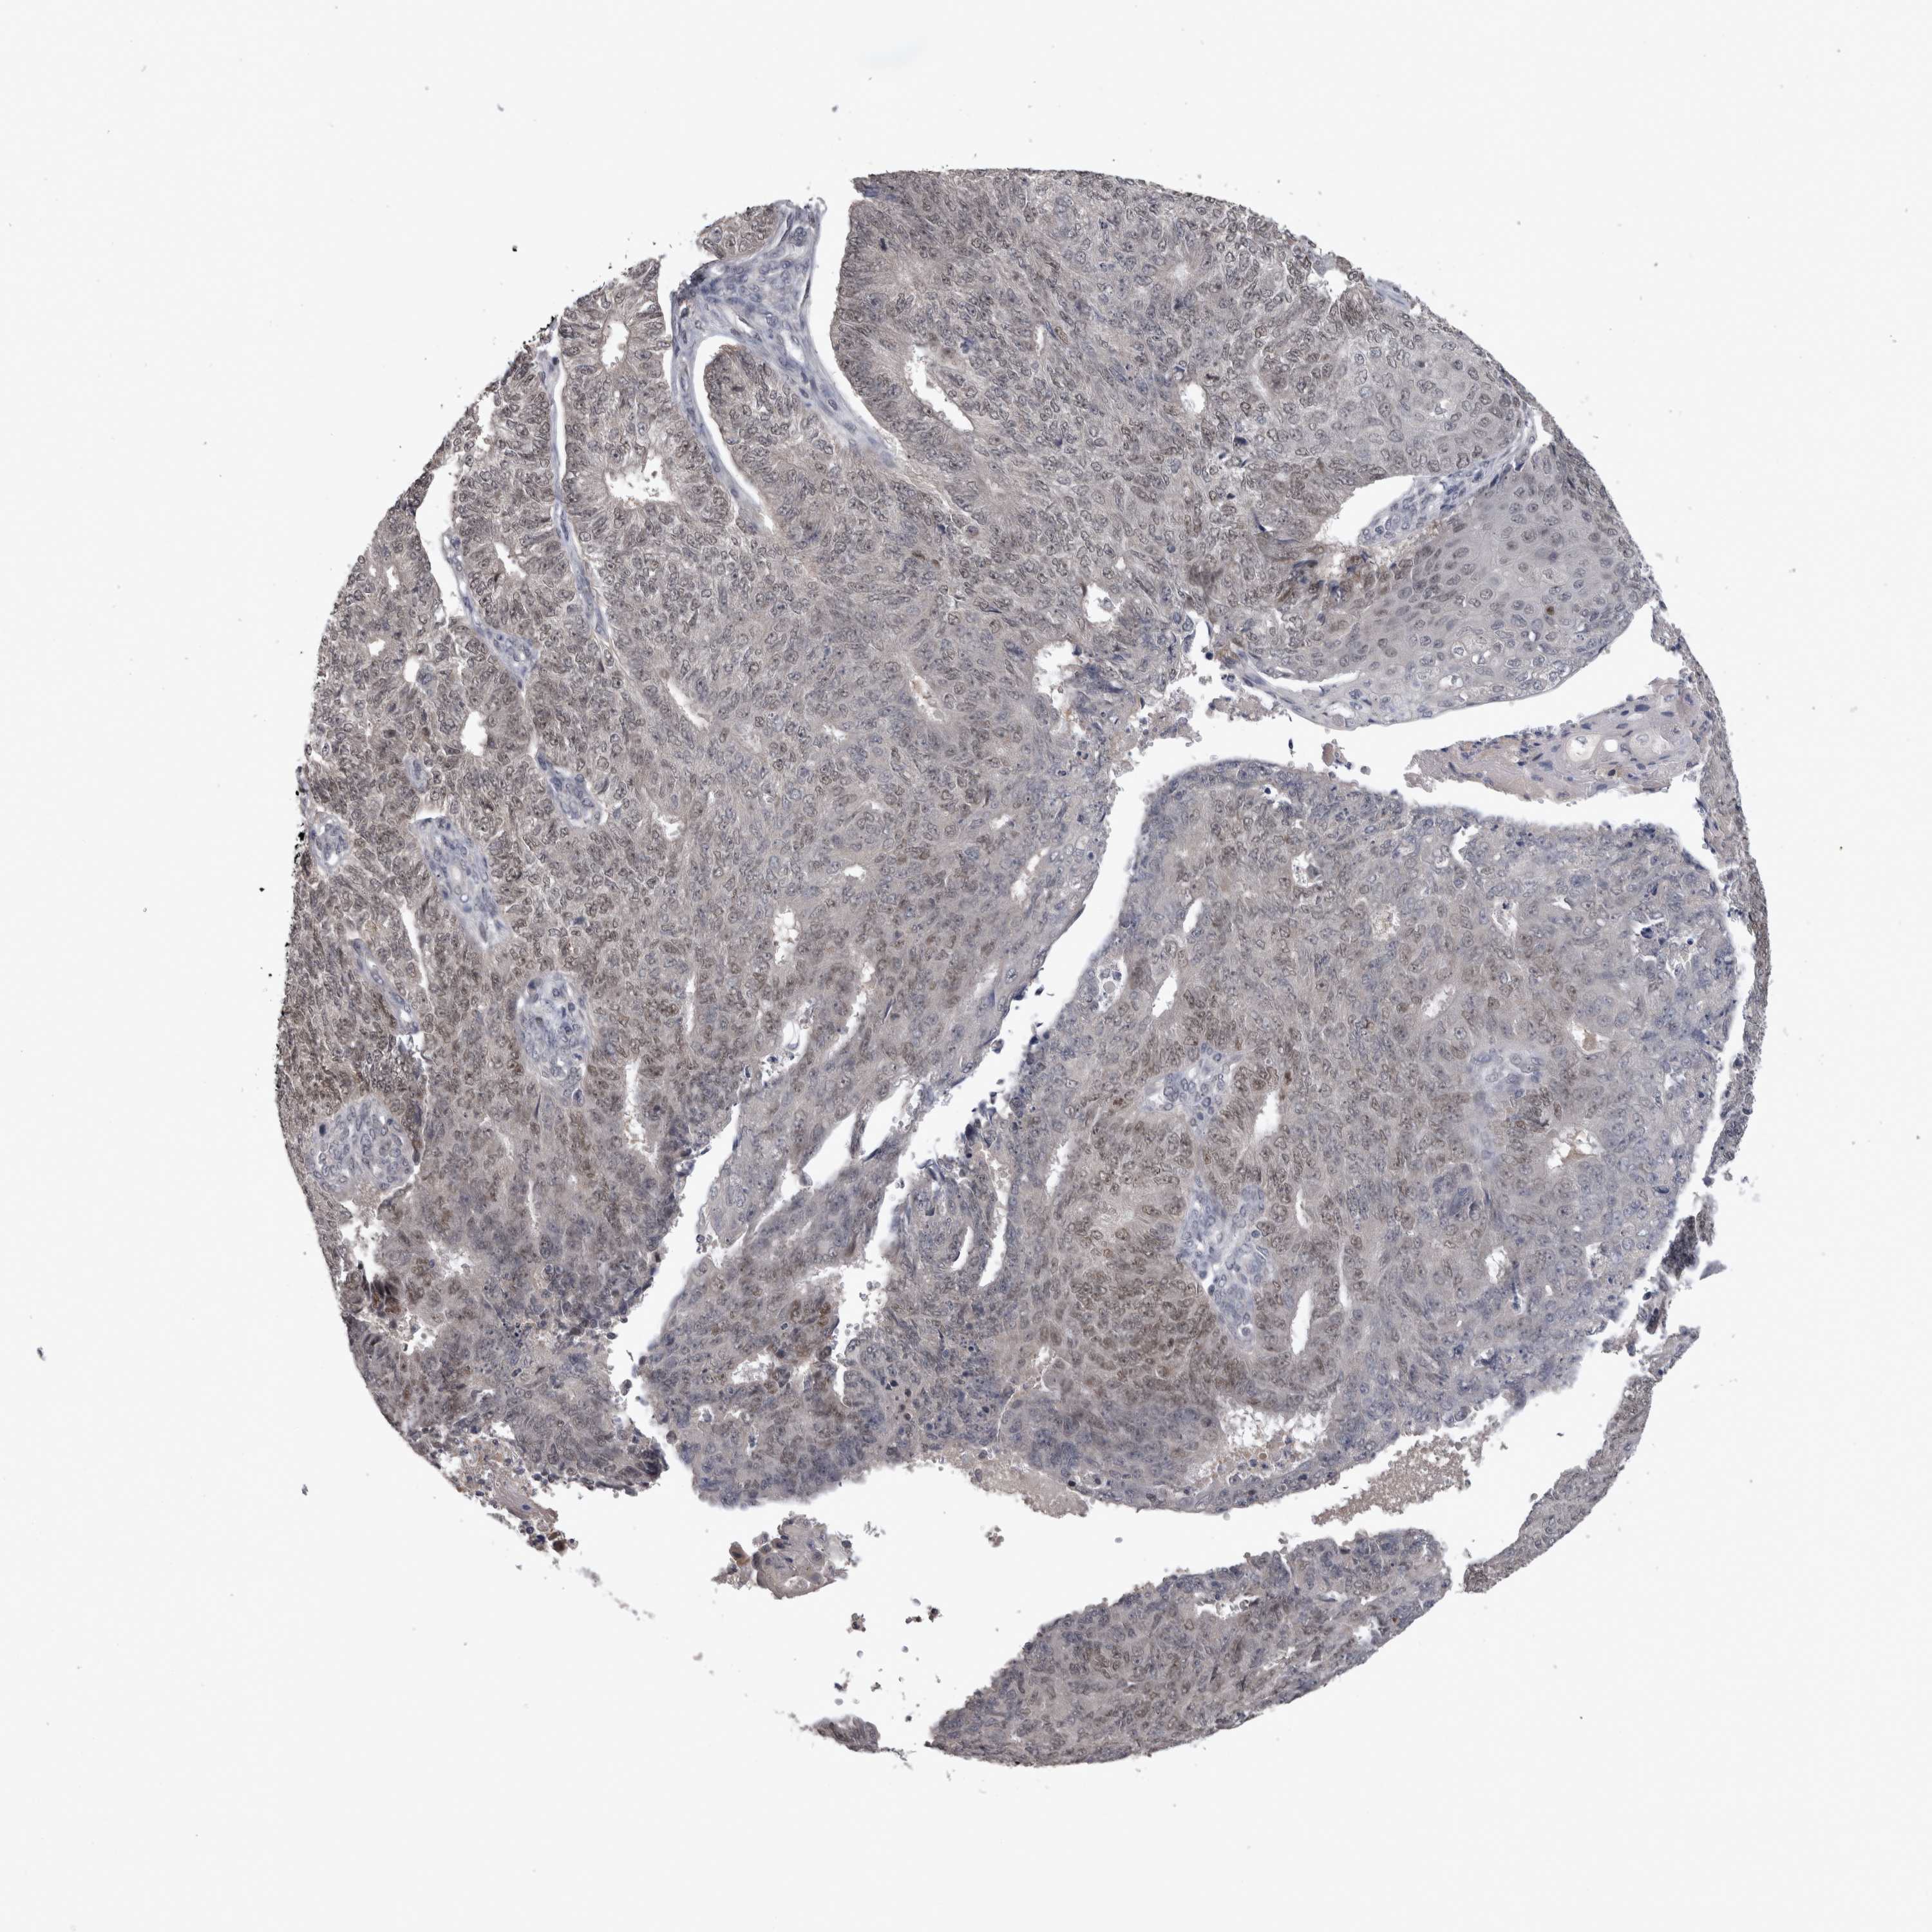

ENDOMETRIAL CANCER - Protein expressioni

A mouse-over function shows sample information and annotation data. Click on an image to view it in a full screen mode. Samples can be filtered based on level of antibody staining by selecting one or several of the following categories: high, medium, low and not detected. The assay and annotation is described here.

Note that samples used for immunohistochemistry by the Human Protein Atlas do not correspond to samples in the TCGA dataset.

Antibody stainingi

Antibody staining in the annotated cell types in the current human tissue is reported as not detected, low, medium, or high, based on conventional immunohistochemistry profiling in selected tissues. This score is based on the combination of the staining intensity and fraction of stained cells.

Each image is clickable and will lead to virtual microscopy that enables deeper exploration of all samples and also displays staining intensity scores, fraction scores and subcellular localization as well as patient and tissue information for each sample.

Antibody HPA025019

Antibody HPA029553

Staining

High

Medium

Low

Not detected

Intensity

Strong

Moderate

Weak

Negative

Quantity

>75%

75%-25%

<25%

None

Location

Nuclear

Cytoplasmic/membranous

Cytoplasmic/membranous,nuclear

Adenocarcinoma, NOS